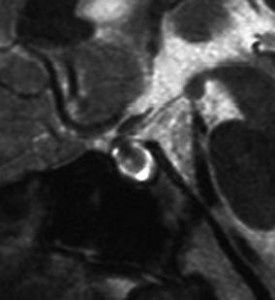

増大しても下垂体症状を出さなかった例

9歳の女の子に偶然発見された腫瘍です。何の症状もありませんでした。頭蓋咽頭腫と診断されて経過観察となりました。1年半観察しましたが腫瘍は増大して,視交差の変形が増して両耳側1/4半盲となり症候性となりました。下垂体機能は正常でした。

上のT2強調画像では,全体的に低信号で,高信号の部分が混在します。上右のCISS画像では,下垂体組織が右に変移していることが推定されます。

左がT1強調画像で高信号,右がT1ガドリニウム増強像ですが腫瘍は増強されません。正常か錐体が腫瘍の右側にくっついていて,ガドリニウム増強されています。典型的なトルコ鞍部黄色肉芽腫です。画像診断で,下垂体腺腫の腫瘍内出血とよく間違われるのですが,高信号になるのはコレステリン結晶を豊富に含むからです。ガドリニウム増強される部分がほとんどないという所見が頭蓋咽頭腫とは異なるところでしょう。

左と中央の画像でinfundibular recessの管腔が見え,左の視交差から視索の変形が強いことが解ります。右の画像では下垂体組織がトルコ鞍の右側に偏在してあります。画像では正常化錐体と明瞭な境界があるように見えるのですが,実際の手術所見では正常下垂体との境界は不鮮明でした。腫瘍のう胞からは黒褐色の内容液 machinery oil とコレステリン結晶が流出しました。厚いのう胞壁は硬膜と下垂体に強く付着して剥離するのが困難で切断して摘出しました。ラトケのう胞とはのう胞壁の厚さが異なると言えます。